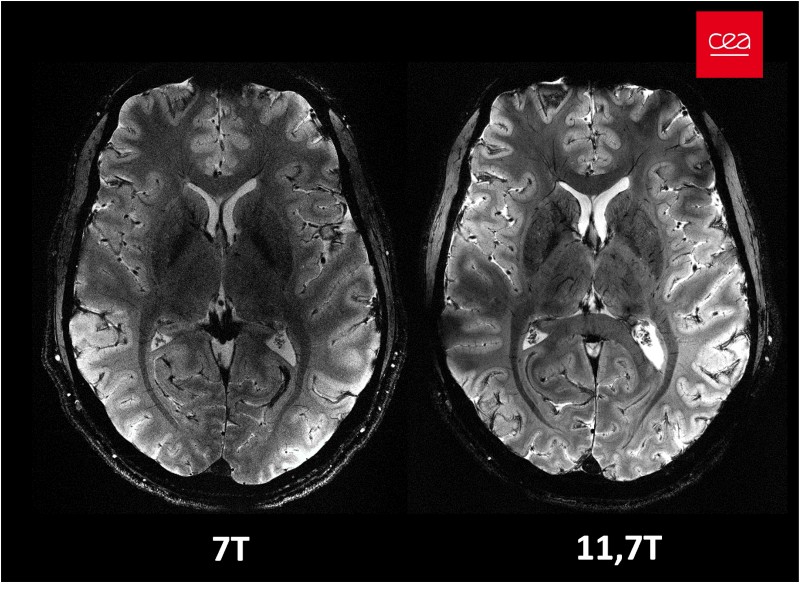

In vivo imaging of the human brain with the Iseult 11.7-T MRI scanner

Nature Methods. 2024. doi: 10.1038/s41592-024-02472-7.

First in vivo images of the human brain revealed with the Iseult 11.7T MRI scanner

Opening New Horizons With The First Human Brain In Vivo Experiments At 11.7T

Proceedings of the ISMRM 2024, Singapore, p0523.